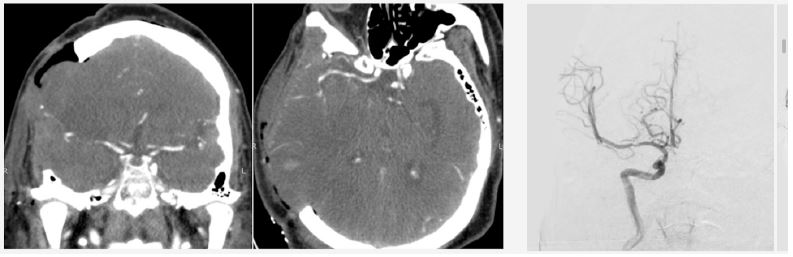

Investigations: Non-contrast CT revealed ischemic changes in the right MCA territory with an Alberta Stroke Program Early CT Score (ASPECTS) score of 6 (Figure 1). The patient was deemed ineligible for pharmacological or mechanical recanalization due to exceeding the therapeutic window.

Figure 1: Computed tomography scan upon patient admission. Evidence of ischemic stroke due to right MCA occlusion is observed.